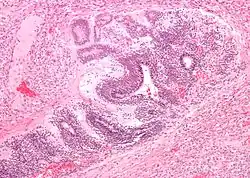

| Micrograph of the primitive neuroepithelium of an immature teratoma of the mediastinum. H&E stain. | |